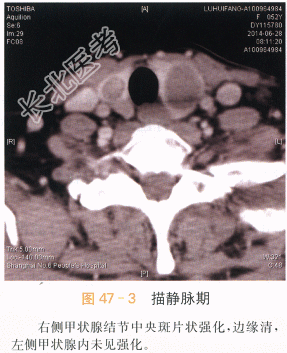

- [材料题] 患者女性,52岁,发现双侧甲状腺结节2年,近期左侧结节增大。体格检查:双侧甲状腺增大,内部扪及多个结节,质韧,活动。实验室和辅助检查TSH5.59IU/ml,T、T正常。超声:双侧甲状腺多个混合性回声结节,形态规则,边缘尚清。左侧结节CDFI未见血流。右侧结节少许血流信号。影像学资料如图所示。